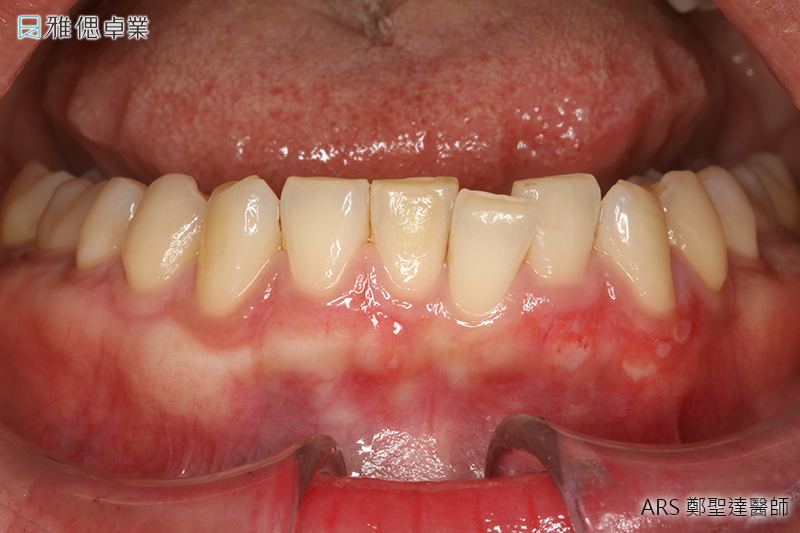

水雷射牙齦美白

- 以水結合雷射切割,切除暗沉牙齦

- 微創治療傷口更小,有效降低出血量

- 精準及細緻的切割,對牙周組織傷害較小

- 刺激牙齦組織再生進而達到牙齦美白的效果

若是配戴金屬假牙的病患,即使接受牙齦美白,仍須更換其他材質如陶瓷的假牙,才能避免黑色素再次沈澱。另外,牙周病的患者牙齦可能發炎、紅腫,必須先治療牙周病,才能接受牙齦美白。

實際案例水雷射牙周病治療術前術後對照